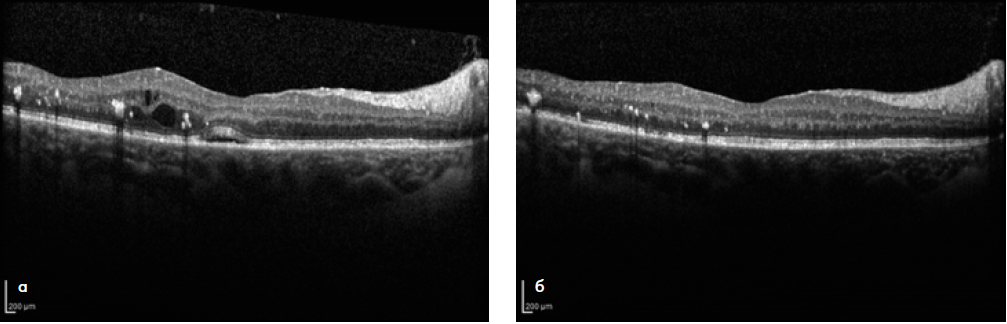

Клиническую оценку безопасности технологии комбинированного лазерного лечения ДМО проводили на основе данных аутофлюоресценции (АФ) в коротковолновом и инфракрасном режимах, а также показателей СЧ по результатам компьютерной микропериметрии. Так, в срок наблюдения 1 месяц было отмечено образование точечных очагов лазериндуцированного повреждения слоя РПЭ (гипер-АФ) в участках, соответствующих зонам порогового лазерного воздействия. В фовеальной аваскулярной зоне, где проводилось только СМЛВ, подобных изменений выявлено не было (рис. 1 а, б). При сравнении АФ-картины в динамике признаков дополнительного повреждения слоя РПЭ в результате повторных сеансов СМЛВ не было выявлено ни в одном из случаев (рис. 2 а, б). По данным компьютерной микропериметрии, в течение всего срока наблюдения образования абсолютных скотом в зонах лазерного воздействия также не наблюдалось во всех случаях (рис. 3 а, б).

Рис. 1. АФ-картина глазного дна пациентки Ц. в коротковолновом (а) и инфракрасном (б) режимах в срок 1 месяц от начала лечения. Точечные очаги гипер-(а) и гипофлюоресценции (б) соответствуют зонам лазеркоагуляции по площади макулярного отека. В фовеальной аваскулярной зоне признаки лазериндуцированных повреждений отсутствуют.

Рис. 4. Оптическая когерентная томография макулярной зоны до начала лечения (а) и через 12 месяцев после комбинированного лазерного воздействия (б). За период наблюдения проведено 2 дополнительных сеанса СМЛВ. Отмечаются уменьшение толщины сетчатки, резорбция серозной отслойки нейроэпителия в фовеа, исчезновение интраретинальных кист.